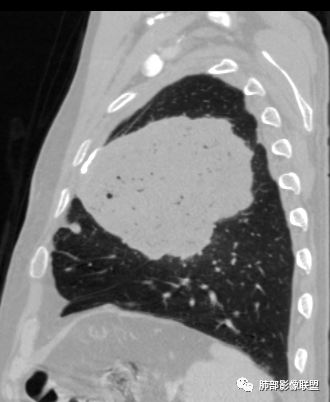

左肺上叶大肿块,膨胀性生长,边界清,密度较低,见部分坏死区,强化弱,肿块见支气管充气V扩张征,分布僵直,枯树枝特点,另一个重要特点血管造影征,淋巴瘤,肿块长轴与胸膜平行,与隐球菌鉴别,隐球荚膜抗原检查,明确诊断经皮肺穿刺。另胸膜钙化(问诊既往有无患胸膜炎病史)。

左肺上叶胸膜下肿块,宽基底与胸膜相连,跨叶裂,边缘清晰膨隆,其内支气管充气,部分扩张、僵直,无明显强化,血管造影征,考虑淋巴瘤,鉴别腺癌

左肺胸膜下巨大占位,跨叶裂,宽基底与胸膜相连,胸膜钙化,平扫密度较低,强化不明显,可见内部血管显影,支气管充气征和扩张,考虑为恶性,倾向于淋巴瘤

左侧胸腔巨大肿块,跨叶生长,临近胸膜钙化,边缘模糊,可见支气管影,定位肺内,增强后轻度强化,边缘见血管影,考虑淋巴瘤,鉴别肉瘤

左肺上叶胸膜下肿块,膨胀性生长,边界清晰,密度不均部分坏死,未见强化,病灶内支气管迂曲扩张,病灶长轴与胸膜平行,胸膜下脂肪间隙存在,胸膜钙化,考虑放线菌?毛霉?鉴别淋巴瘤

支持淋巴瘤,左上肺大肿块,有分叶,边缘光整,病灶内密度不均,可见支气管扩张征,增强后可见血管影征。周围肺野清晰。

左肺上叶肿块,宽基底与胸膜相连,跨叶裂,边缘清晰膨隆,可见小分叶,其内支气管充气,部分扩张、僵直,呈枯枝征,支气管达边征,增强无明显强化,可见血管造影征,考虑恶性病变,淋巴瘤,鉴别粘液腺癌。

大肿块,边缘光滑,深分叶

近端支气管堵塞、推移为主

部分类似于脐凹征

内部支气管扩张

肺动脉推移为主,边缘部分进入

大肿块、表面光滑但深分叶,肺门侧支气管堵塞

1)部位:周围型或中央型软组织肿块,以周围型为多见,且肿瘤多位于肺上叶。如本例:该肿瘤位于左肺上叶。

2)大小及形态:由于本病恶性程度高,早期症状不明显,发现时肿块均较大。如本例病变巨大。

3)肿块边界和边缘:多较清楚,呈圆形、类圆形,且由于肿块生长速度不均匀,可见分叶,毛刺少见。有报道肿块周围毛玻璃影是多形性癌特征表现。

4)密度:肿块平扫为软组织密度,由于体积较大,内部常见大片状坏死,可出现不规则厚壁空洞或坏死内多发无壁小空洞,坏死多不均匀:坏死灶内可见如柳絮样的斑片样强化灶,坏死边缘与非坏死区分界不清本例坏死较明显,密度不均匀。